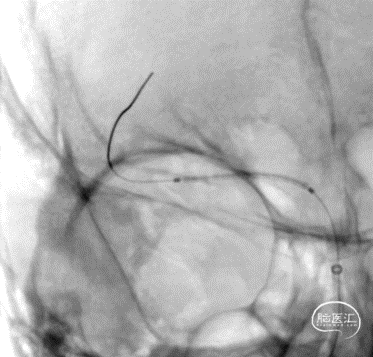

沿微导丝输送赛诺神畅 NOVA颅内药物球扩支架2.25*20mm支架到位,支架输送顺利,全过程无明显张力变化。

6atm缓慢扩张释放支架。

释放支架后造影见支架中段稍有残留狭窄,以8atm缓慢再扩张,残留狭窄消失。